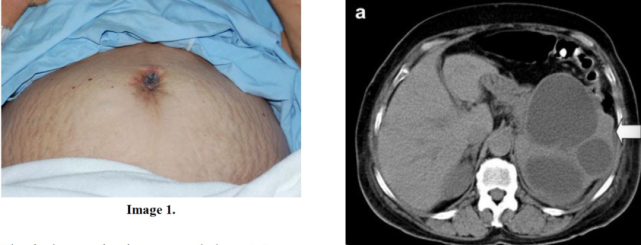

图片

一位有 Sister Mary Joseph’s nodule 的 37 岁女性,CT 示胃部占位伴肝转移,病理证实为印戒细胞癌(图片来自文献 [2])